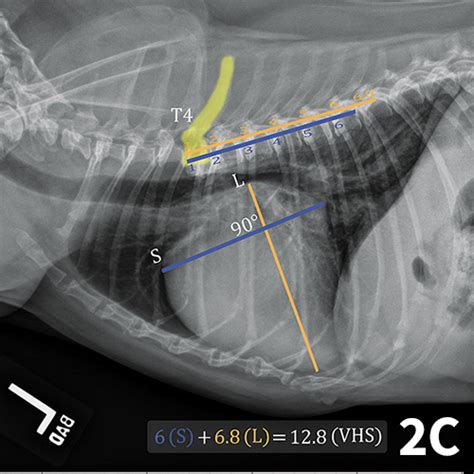

Web an enlarged cardiac silhouette is an indicator of cardiac disease. The published range for normal vhs in cats is 6.7 to 8.1 on lateral radiographs (average,. Web diagram of lateral view of the thorax of a cat illustrating the vertebral heart size measurement method. The vhs is a straightforward measurement of the length of the heart along the spinal cord. However, determination of cardiac size is usually. Web normal vertebral heart scale values. Unlike dogs, a value above 8 is abnormal for cats. Web the vertebral heart scale is measured in the same way for both cats and dogs. Web what is vhs cat?

Web diagram of lateral view of the thorax of a cat illustrating the vertebral heart size measurement method. Web the vertebral heart scale is measured in the same way for both cats and dogs. However, determination of cardiac size is usually. Web normal vertebral heart scale values. The published range for normal vhs in cats is 6.7 to 8.1 on lateral radiographs (average,. Unlike dogs, a value above 8 is abnormal for cats. The vhs is a straightforward measurement of the length of the heart along the spinal cord. Web what is vhs cat? Web an enlarged cardiac silhouette is an indicator of cardiac disease. Web diagram of lateral view of the thorax of a cat illustrating the vertebral heart size measurement method.